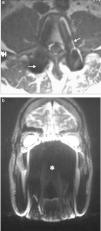

El artificio de Gibbs a menudo funciona como sinónimo del de truncamiento. Consiste en la falta de convergencia de la integral de Fourier como punto de discontinuidad de una función y ocurre en la dirección de fase1,6,14. En este caso, se observan anillos en la proximidad de una discontinuidad (p. ej. en la interfase cerebro/cráneo)1,4,13,15 (fig. 22), por lo que el artificio solo se elimina al remover la discontinuidad de la función. Para ello, se emplean filtros que nivelan o alisan la imagen, incrementando la matriz y extendiendo el tiempo de escaneo1,13.